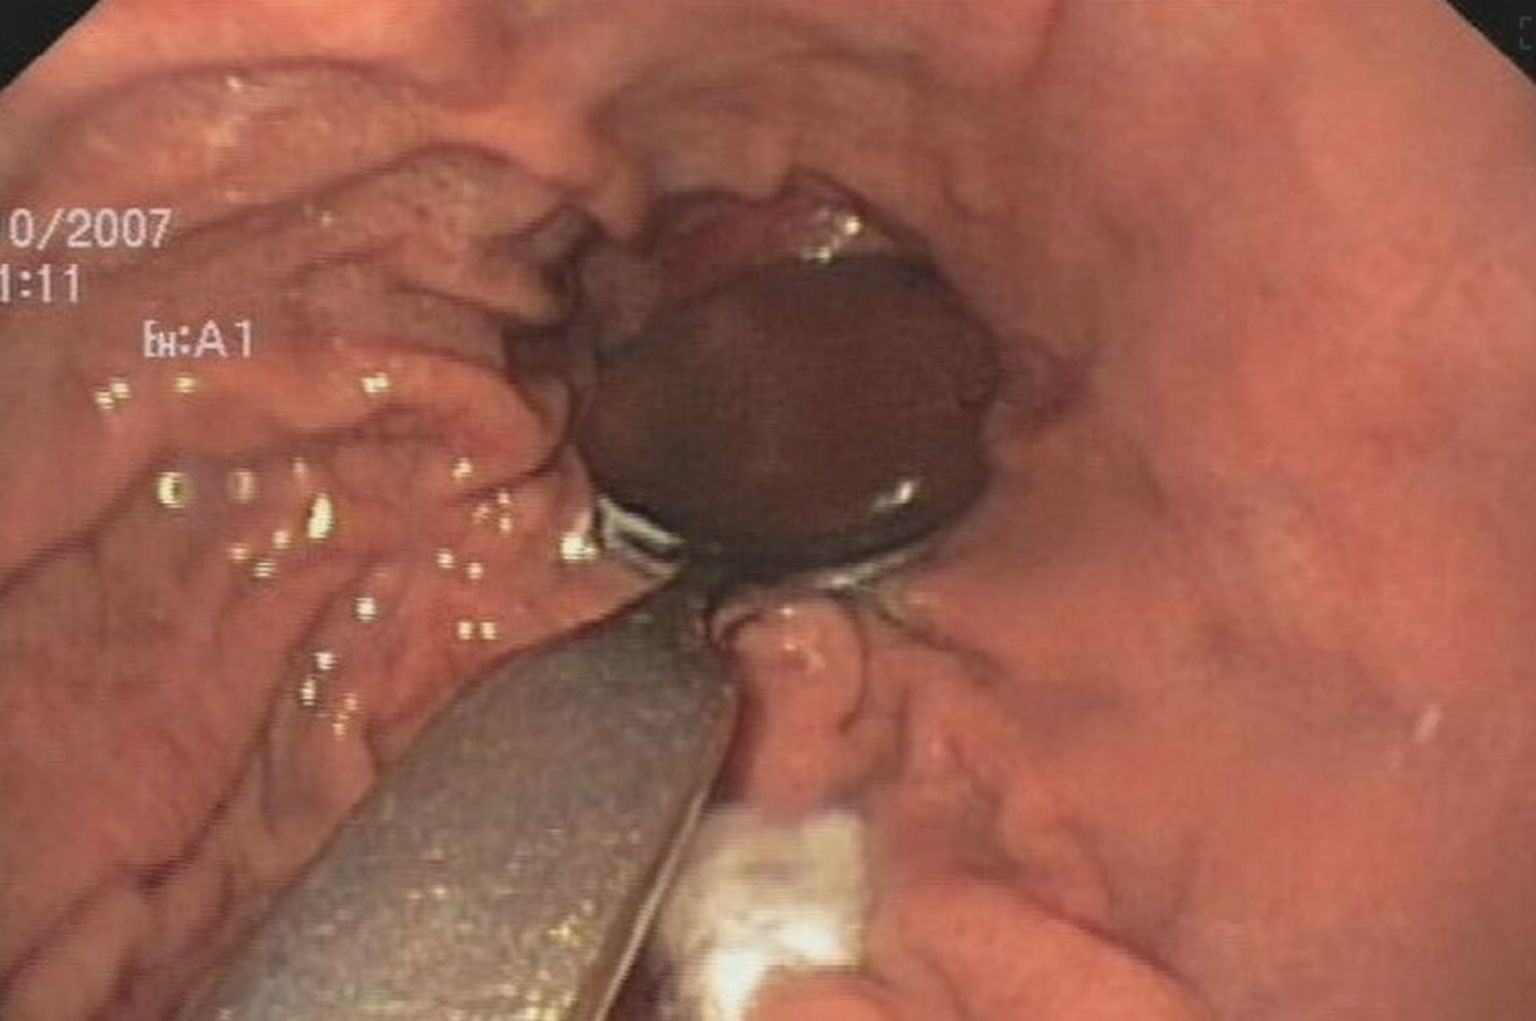

• Strano tijelo u tijelu, ilustracija - 1 Foto: DNEVNIK.hr

• Strano tijelo u tijelu, ilustracija - 2 Foto: DNEVNIK.hr

• Strano tijelo u tijelu, ilustracija - 3 Foto: DNEVNIK.hr

• Strano tijelo u tijelu, ilustracija - 4 Foto: DNEVNIK.hr

• Strano tijelo u tijelu, ilustracija - 5 Foto: DNEVNIK.hr